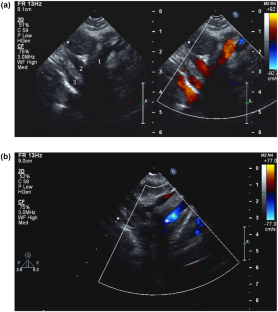

Fig. 2